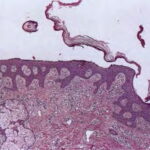

Histopathology. The earliest change consists of acantholysis in the upper epidermis, within or adjacent to the granular layer, leading to a subcorneal bulla in some instances . More commonly, enlargement of the cleft leads to detachment |

of the stratum corneum without bulla being seen. The number of acantholytic keratinocytes is usually small, often requiring a careful search to identify them. Secondary clefts may develop, leading to detachment of the epidermis in its mid level. These clefts may extend to above the basal layer, rarely giving rise to limited areas of suprabasal separation. In the setting of a subcomeal blister, dyskeratotic granular keratinocytes are diagnostic for this disorder. Eosinophilic spongiosis may be prominent with intraepidermal eosinophilic pustules. Thus, the histologic features of pemphigus foliaceus may have three pattems: {a} eosinophilic spongiosis; {b} a subcorneal blister, often with few acantholytic keratinocytes; and {c} a subcorneal blister with dyskeratotic granular keratinocytes , diagnostic of this disorder. The character of the inflammatory infiltrate is variable and depends on the age of the lesion, whether a blister is present, whether the superficial portion of the epidermis has been detached, and whether there is impetiginization or necrosis of the blister roof. |